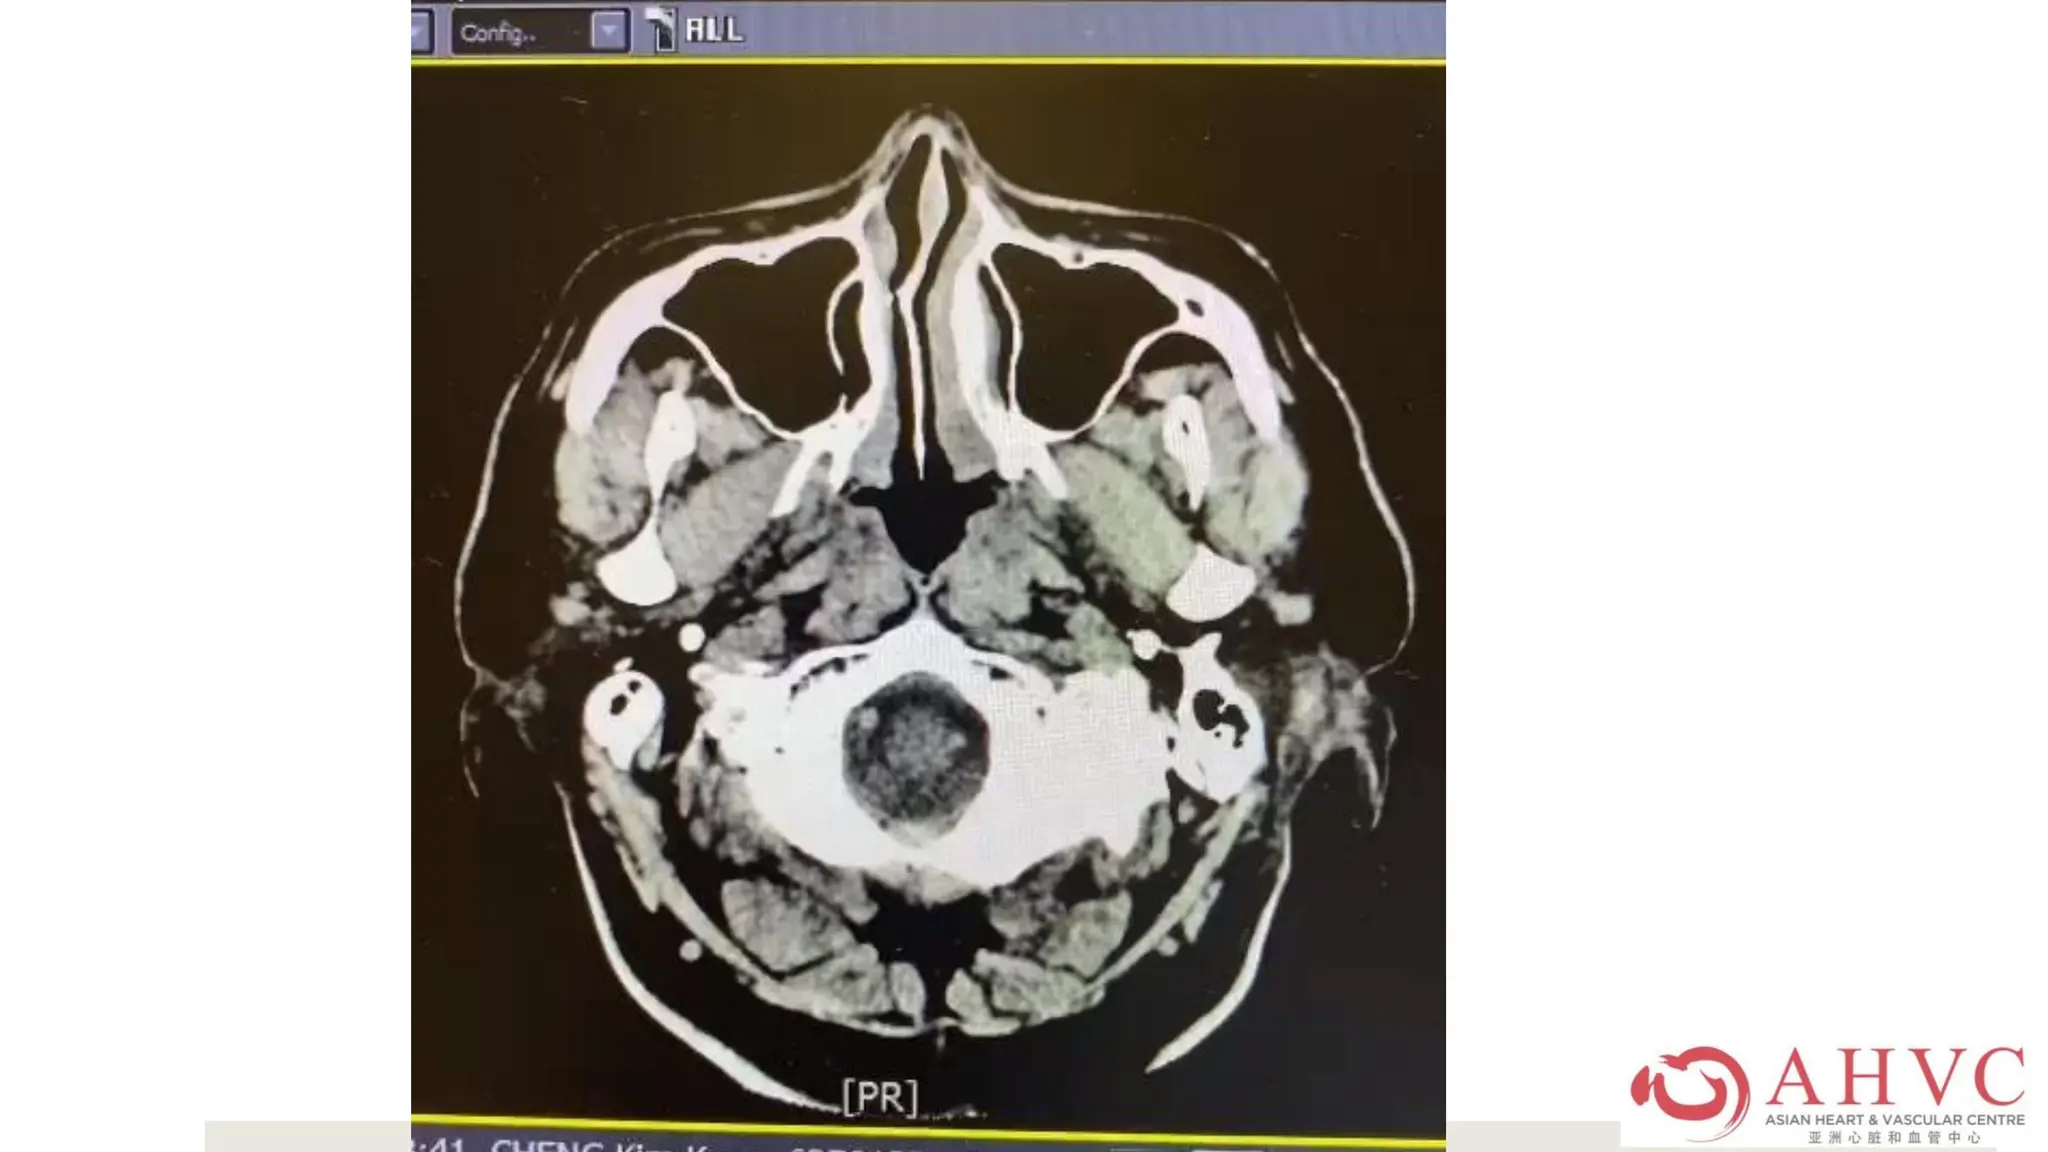

MRI showed acute right cerebellar

stroke.

Now what can I do? Stroke despite

DOAC

Case – MrCKK Cardioversion was successful, he was planned for home the next morning when he suddenly had acute vertigo with incoordination. MRI showed acute right cerebellar stroke. Now what can I do? Stroke despite DOAC